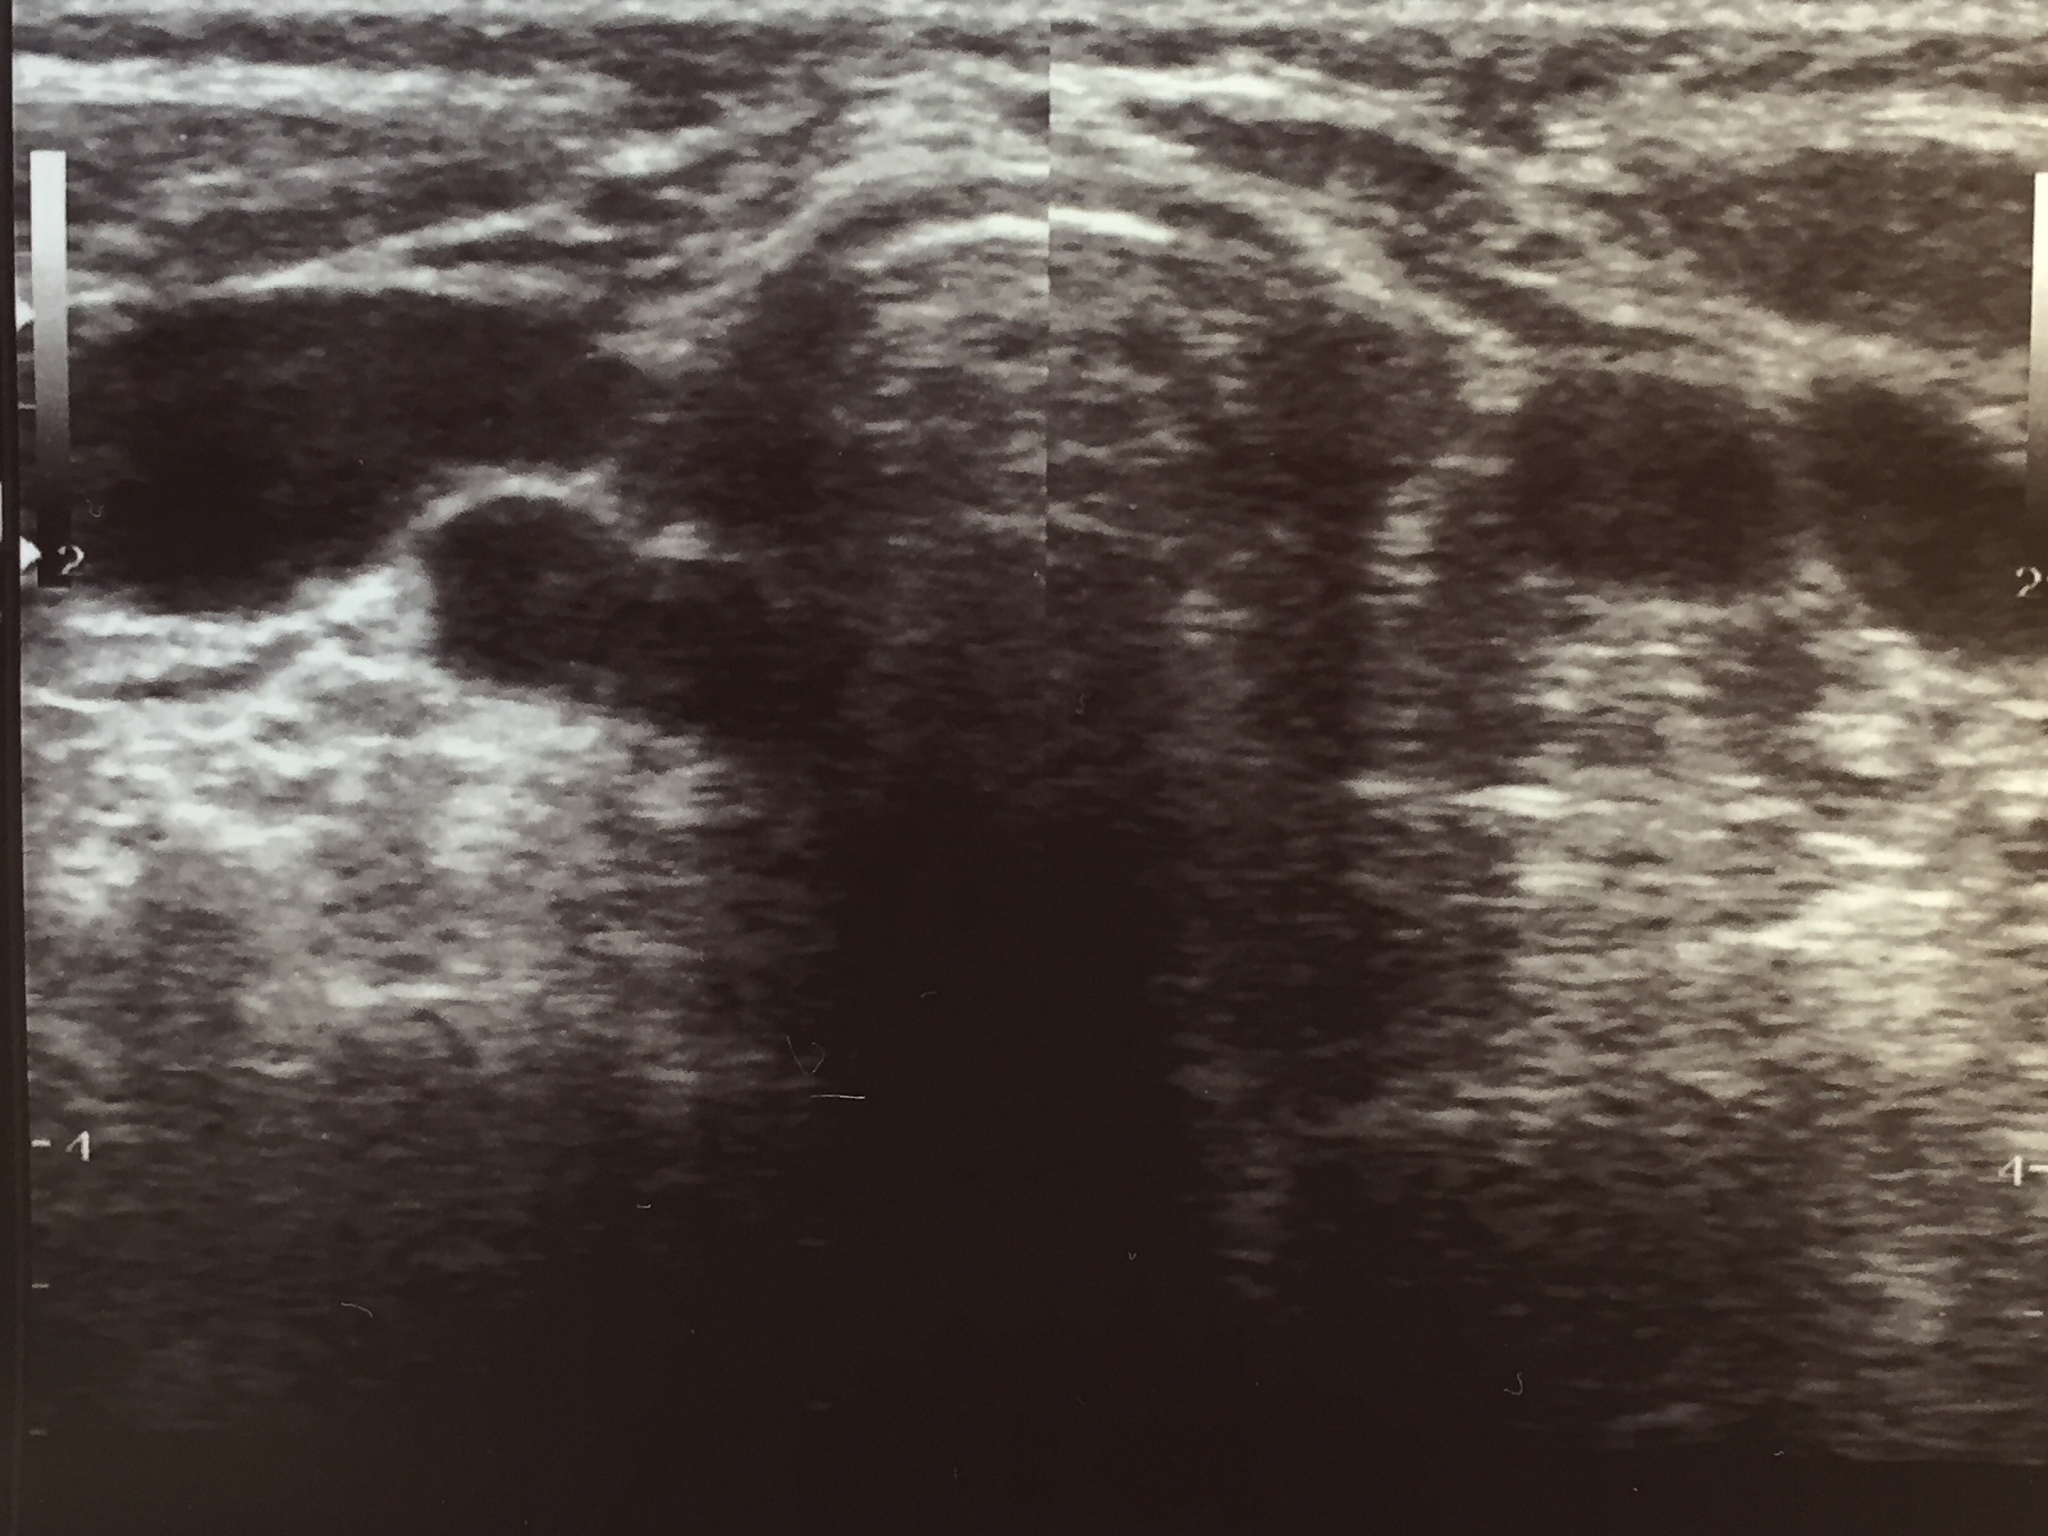

研究发现,颈动脉斑块的远端似乎与微弱的回声存在联系。此外,观察到斑块的远端运动与颈动脉的搏动轻微同步。

颈动脉搏动与斑块远端运动的潜在联系